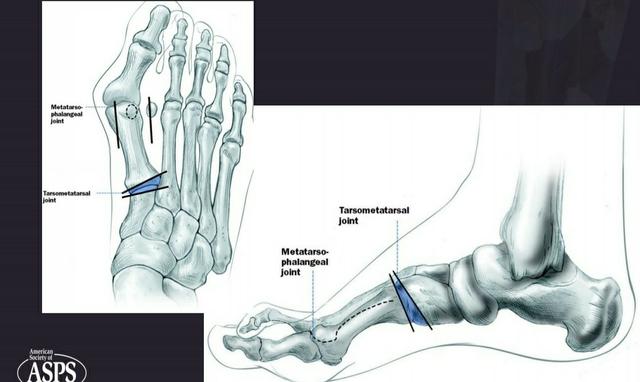

第一个脚趾有三个滑膜关节。第一个关节是跖跗关节位于内侧楔形骨和第一跖骨之间,不允许大幅运动。第二个关节是跖趾关节,连接第一跖骨和第一近端趾骨。该关节允许第一个脚趾的弯曲和伸展,以及向第二个脚趾中心的小幅度的外展和内收。它同时被韧带加强(包括:跖趾侧副韧带和跖板)。最后一个关节是趾间,是第一趾两趾骨之间的连接。这个关节只允许屈曲和伸展,它也被韧带加强。

Austin/Chevron Procedure

这种手术通常用于轻度畸形。截骨术呈“V”形。然后将松动的截骨以不同的方式放置,以纠正第一跖骨角度。截骨块用克氏针或螺钉固定。

Scarf Procedure

当畸形中等至严重时,Scarf Procedure是常用的选择。从内向外沿跖骨干纵轴截骨。将跖骨头截骨块移向外侧,并用两个螺钉固定。

Closing Base Wedge Procedure

该手术主要用于严重的畸形。在跖骨近端外侧做楔形截骨。当楔块被移除时,远端部分被转移到外侧,导致间隙闭合,第一跖骨与第二跖骨对齐。双皮质螺钉固定。

Lapidus关节融合术

当观察到严重的畸形时,这是另一种选择。通过切除内侧楔形关节软骨和第一跖骨基部,两者融合。用钢板或螺钉固定。